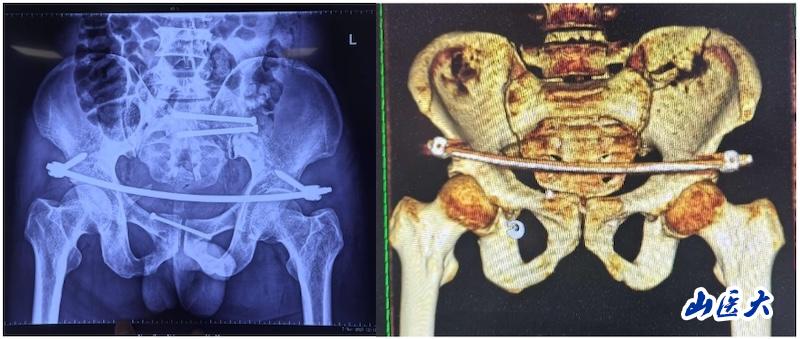

近日,我校第二医院骨科成功为一位骨盆骨折患者实施了UCRT解锁复位术,术中,医务人员结合先进的O-arm术中影像系统和天玑机器人技术,实现了微创治疗骨盆骨折的新突破。

该患者在驾驶三轮车时发生车祸,导致骨盆骨折,经过当地医院对症治疗后转入我校第二医院急诊科。由于血色素持续下降,血管外科首先进行了血管介入栓塞处理,随后转入骨科创伤病区,由孙海钰团队接续治疗。经过详细检查和评估,孙海钰主任、贺冬冬副主任医师、王欢副主任医师为患者制定了运用UCRT解锁复位技术,结合天玑机器人及O-arm术中影像系统为其实施骨盆闭合复位的手术治疗方案。3月6日,孙海钰团队在骨科老一辈专家尹芸生主任的指导及麻醉师、技师、器械护士和巡回护士的通力协助下,成功运用微创新技术为患者实施了手术。

据孙海钰介绍,骨盆髋臼骨折是一种严重的创伤,传统开放复位内固定术创伤大、恢复慢,而闭合复位则具有微创、出血少、恢复快等优点。随着医疗技术的不断进步,UCRT解锁复位技术结合天玑机器人及O-arm术中影像系统为骨盆骨折治疗提供了更加精准、微创的解决方案,该技术代表了当前骨盆骨折治疗的前沿方向。